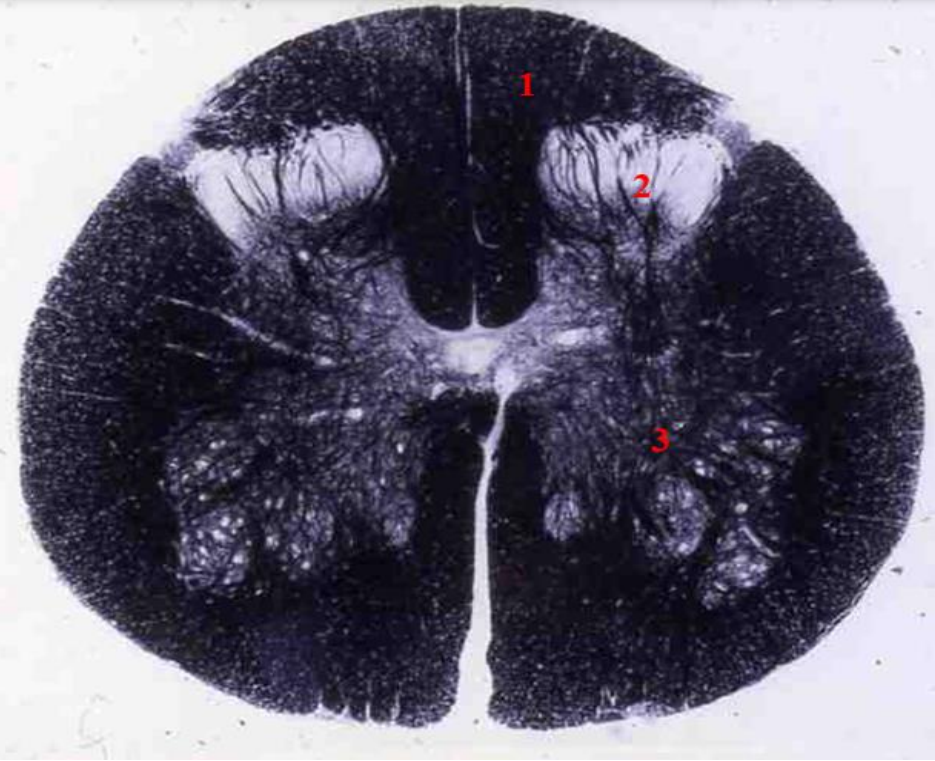

Q

indentify the weigert

A

cervical cord

- fibre tracts are larger

- grey matter is large

- brachial plexus

- no lateral horn

12

1

fasiculus gracilis

13

2

fasciculus cuneatus

14

3

posterior horn

15

4

anterior horn